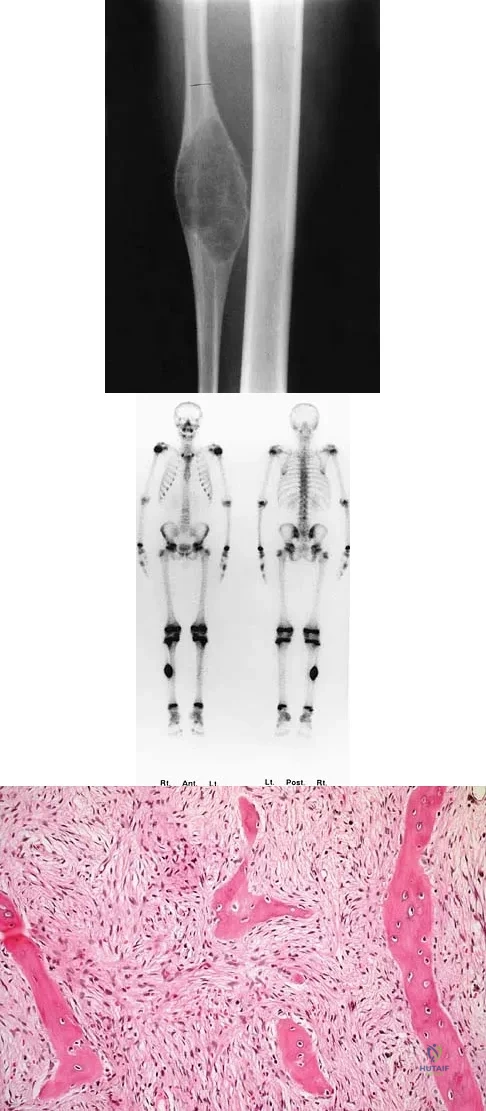

A 10-year-old child has leg discomfort with activity. A radiograph, bone scan, and biopsy specimen are shown in Figures 1a through 1c. What is the most likely diagnosis?

Explanation

The ground glass appearance on the radiograph, the hot bone scan, and histologic findings of bony spicules without osteoblastic rimming in a background of bland fibrous tissue all suggest fibrous dysplasia. Stress-related pain is common with activity because of the dysplastic bone. Parosteal osteosarcomas are surface lesions. Simple cysts, aneurysmal bone cysts, and eosinophilic granuloma are all possible radiographically; however, the histology is most consistent with fibrous dysplasia. Harris WH, Dudley HR Jr, Barry RS: The natural history of fibrous dysplasia: An orthopaedic, pathological and roentgenographic study. J Bone Joint Surg Am 1962;44:207.

References:

- Campanacci M: Bone and Soft Tissue Tumors. Vienna, Austria, Springer-Verlag, 1990.